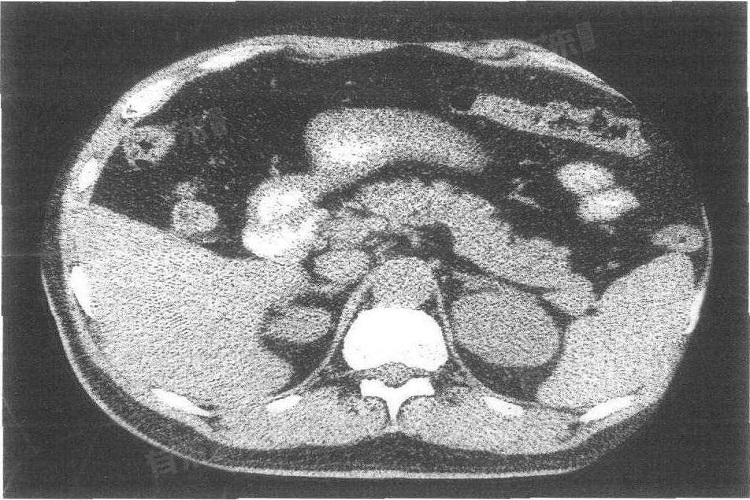

2、肾上腺囊肿:能清楚显示肾上腺囊肿的大小、数目、位置及囊壁情况。囊肿在CT上表现为边界清晰、密度均匀的低密度影,通过CT检查可与其他肾上腺占位性病变相鉴别,为诊断和治疗提供准确信息。

此外,肾上腺CT可精准发现肾上腺部位的肿瘤。无论是良性的腺瘤,还是恶性的肾上腺皮质癌、嗜铬细胞瘤等,CT都能明确肿瘤的大小、形状、位置及与周围组织的关系。通过测量肿瘤密度,还能初步判断肿瘤性质,为后续治疗方案制定提供关键依据。